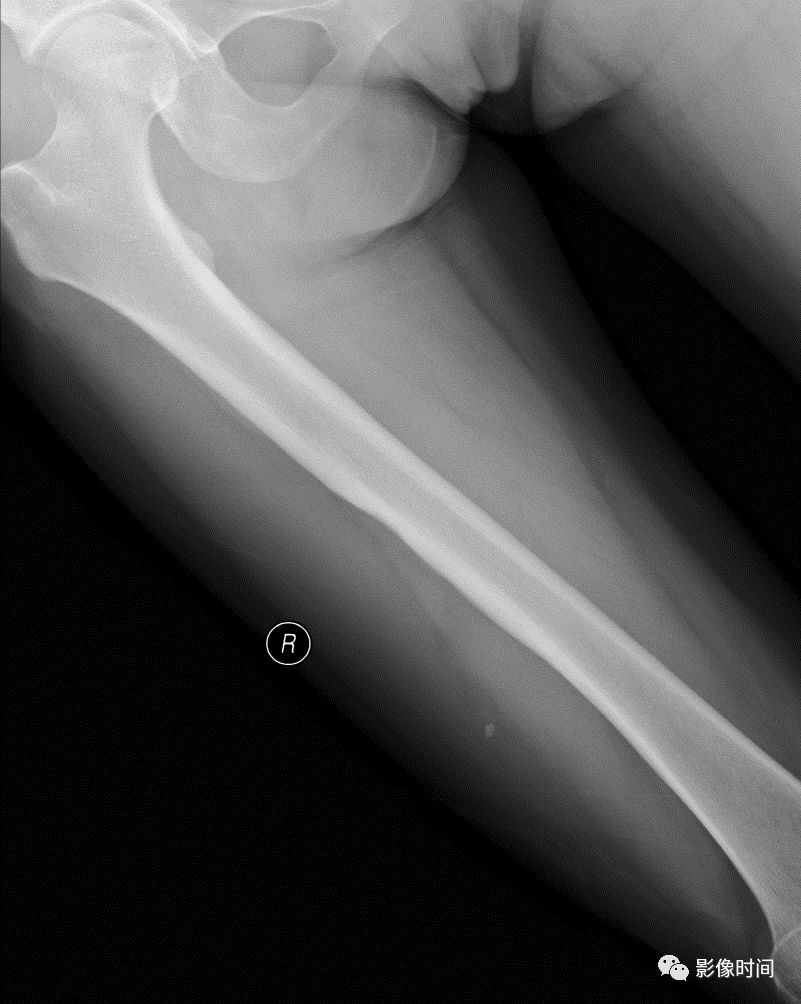

(三)浸润性破坏  浸润性骨破坏(图 9、图 10、图 11)是肿瘤组织沿哈弗氏管呈浸润性生长侵蚀骨与骨髓的结果。往往是分化很差、高度间变、异型性明显的肿瘤组织对骨的侵蚀。

影像学表现为筛孔样、虫蚀样(皮质骨)、渗透样、斑片状(松质骨)和大片溶骨性破坏,其破坏特点是肿瘤边缘模糊,境界不清,与正常骨无明显界限且有融合成片的倾向。

这种不同形态的骨破坏主要是肿瘤对骨侵蚀的程度和部位不同所决定的,不能作为肿瘤定性诊断的依据。

图 9  浸润性破坏:骨肉瘤